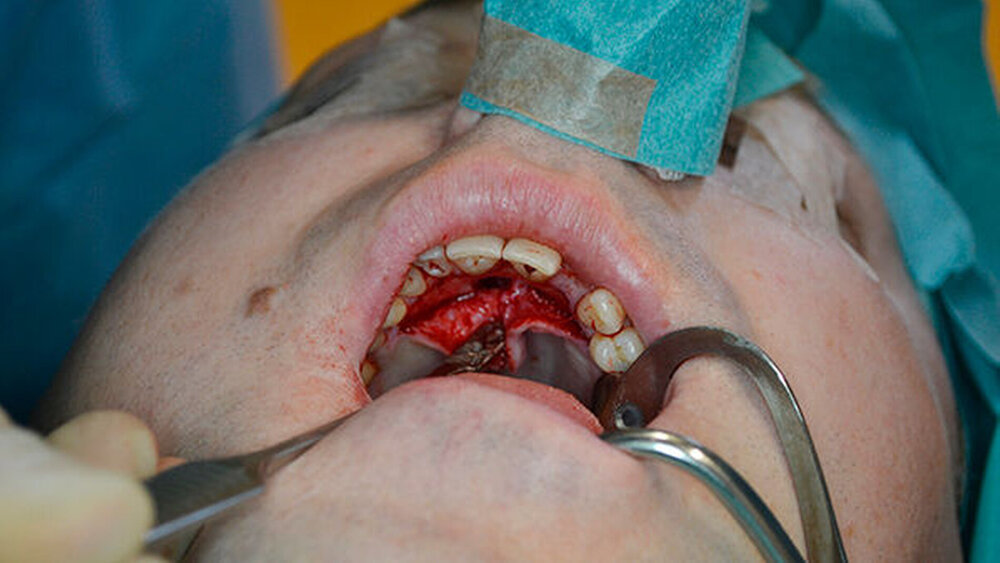

Zur weiteren Abklärung erfolgte eine dreidimensionale Bildgebung mittels DVT (Abbildung 3). Hier zeigte sich eine gut abgrenzbare Raumforderung im Bereich der Oberkieferfront mit Kontakt zum Canalis incisivus. Es wurde eine Zystektomie mit palatinaler Aufklappung in Kombination mit einer Beckenkammaugmentation durchgeführt. Intraoperativ kam es nach Injektion der Lokalanästhesie zu einem Spontanprolaps eines Idoformstreifens palatinal (Abbbildung 4).

Die Zyste wurde in toto exstipiert und zur weiteren Diagnostik in die Pathologie abgegeben (Abbildung 5). Auf Grund eines Zystenvolumens von mehr als 2cm3in der DVT-Diagnostik wurde eine Knochenaugmentation mittels Beckenkammspongiosa durchgeführt. Nach enoralem Wundverschluss wurde ein Überknüpfverband mittels Iodoformvaselinestreifen angelegt und mittels Drahligaturen interdental fixiert (Abbildung 6).